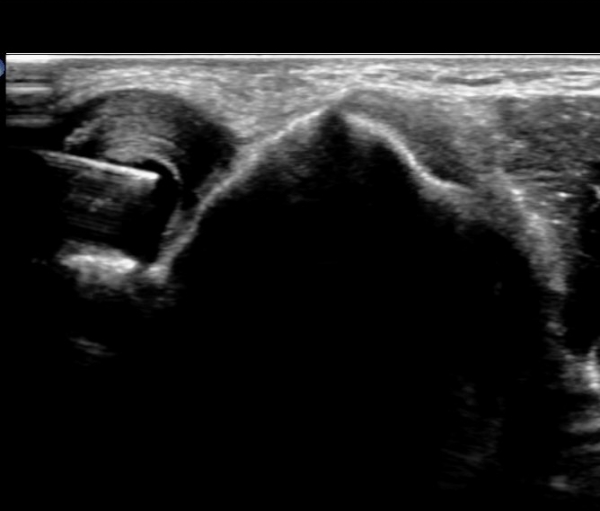

Áֵοͳ» ÁÖ»çÄ¡·á¸¦ À§ÇØ È¯ÀÚ¸¦ ¿·À¸·Î ´¯°ÔÇÏ°í ÆÈ²ÞÄ¡¸¦ Æí »óÅ¿¡¼­ ¸ö ¿·¿¡ ÆÈÀ» ´ë°í ŽÃËÀÚ¸¦

ÁֵοͿ¡ ȾÀ¸·Î ´í »óÅ¿¡¼­ ¼ö¾×Àú·ù°¡ °¡Àå Àß º¸ÀÌ°í ¼ö¾× Àú·ù¿¡ Áֻ簡 °¡´ÉÇÑ À§Ä¡¿¡¼­

¼ö¾×Àú·ù¸¦ È®ÀÎÇÑ´Ù(»çÁø 6)

»çÁø 8, 9)ÀÇ ÀÚ¼¼¿¡¼­ Ãà¹æÇâ ¹æ¹ýÀ¸·Î ¼ö¾×³»¿¡ Áֻ縦 ½ÃÇàÇÑ´Ù(»çÁø 7, ÷ºÎ µ¿¿µ»ó)